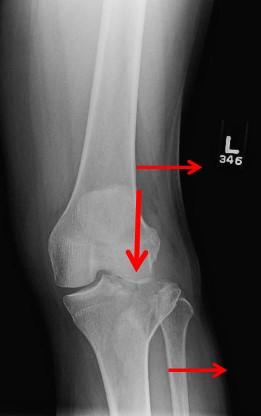

Променева діагностика переломів проксимального відділу кісток гомілки

Рентгенографія у трьох проекціях є первинним методом діагностики, проте часто недостатньо інформативна для оцінки характеру внутрішньосуглобового перелому.

Пряма, бокова, коса проекції